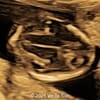

A 33-year-old nullipara with non-contributory medical history presented at 20 weeks, 6 days based on an early scan. Ultrasound revealed the following findings. There were no other apparent abnormalities. What is the most probable diagnosis?